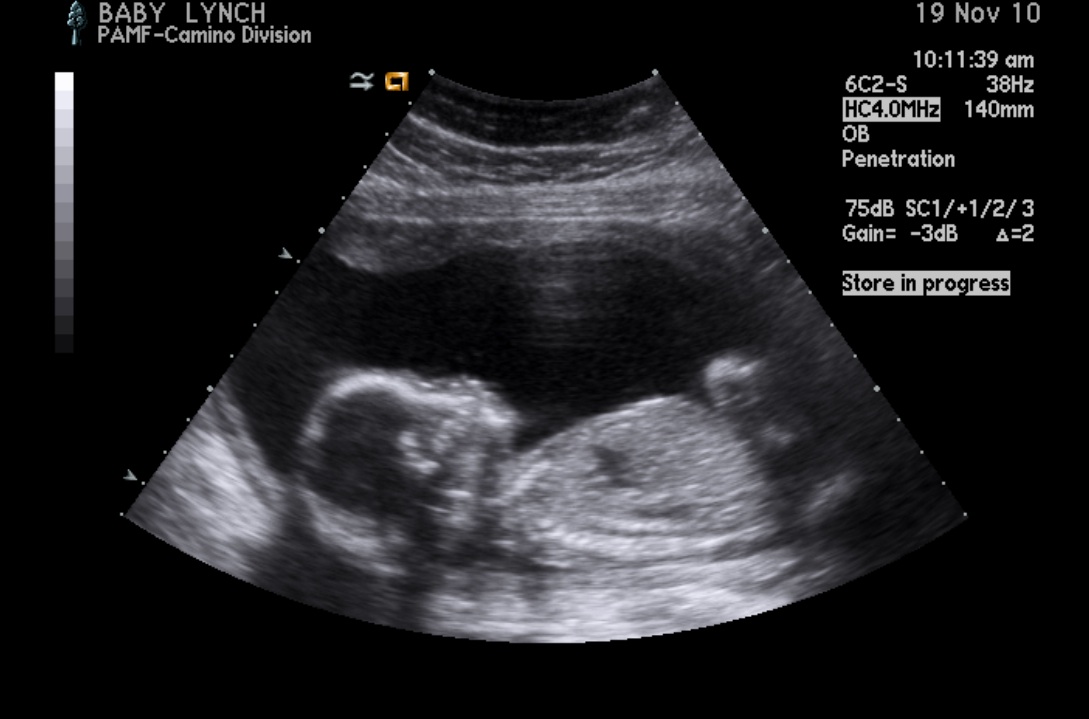

So this little picture is the clearest one we have. At this time, baby was actually moving it's mouth as if it was talking.